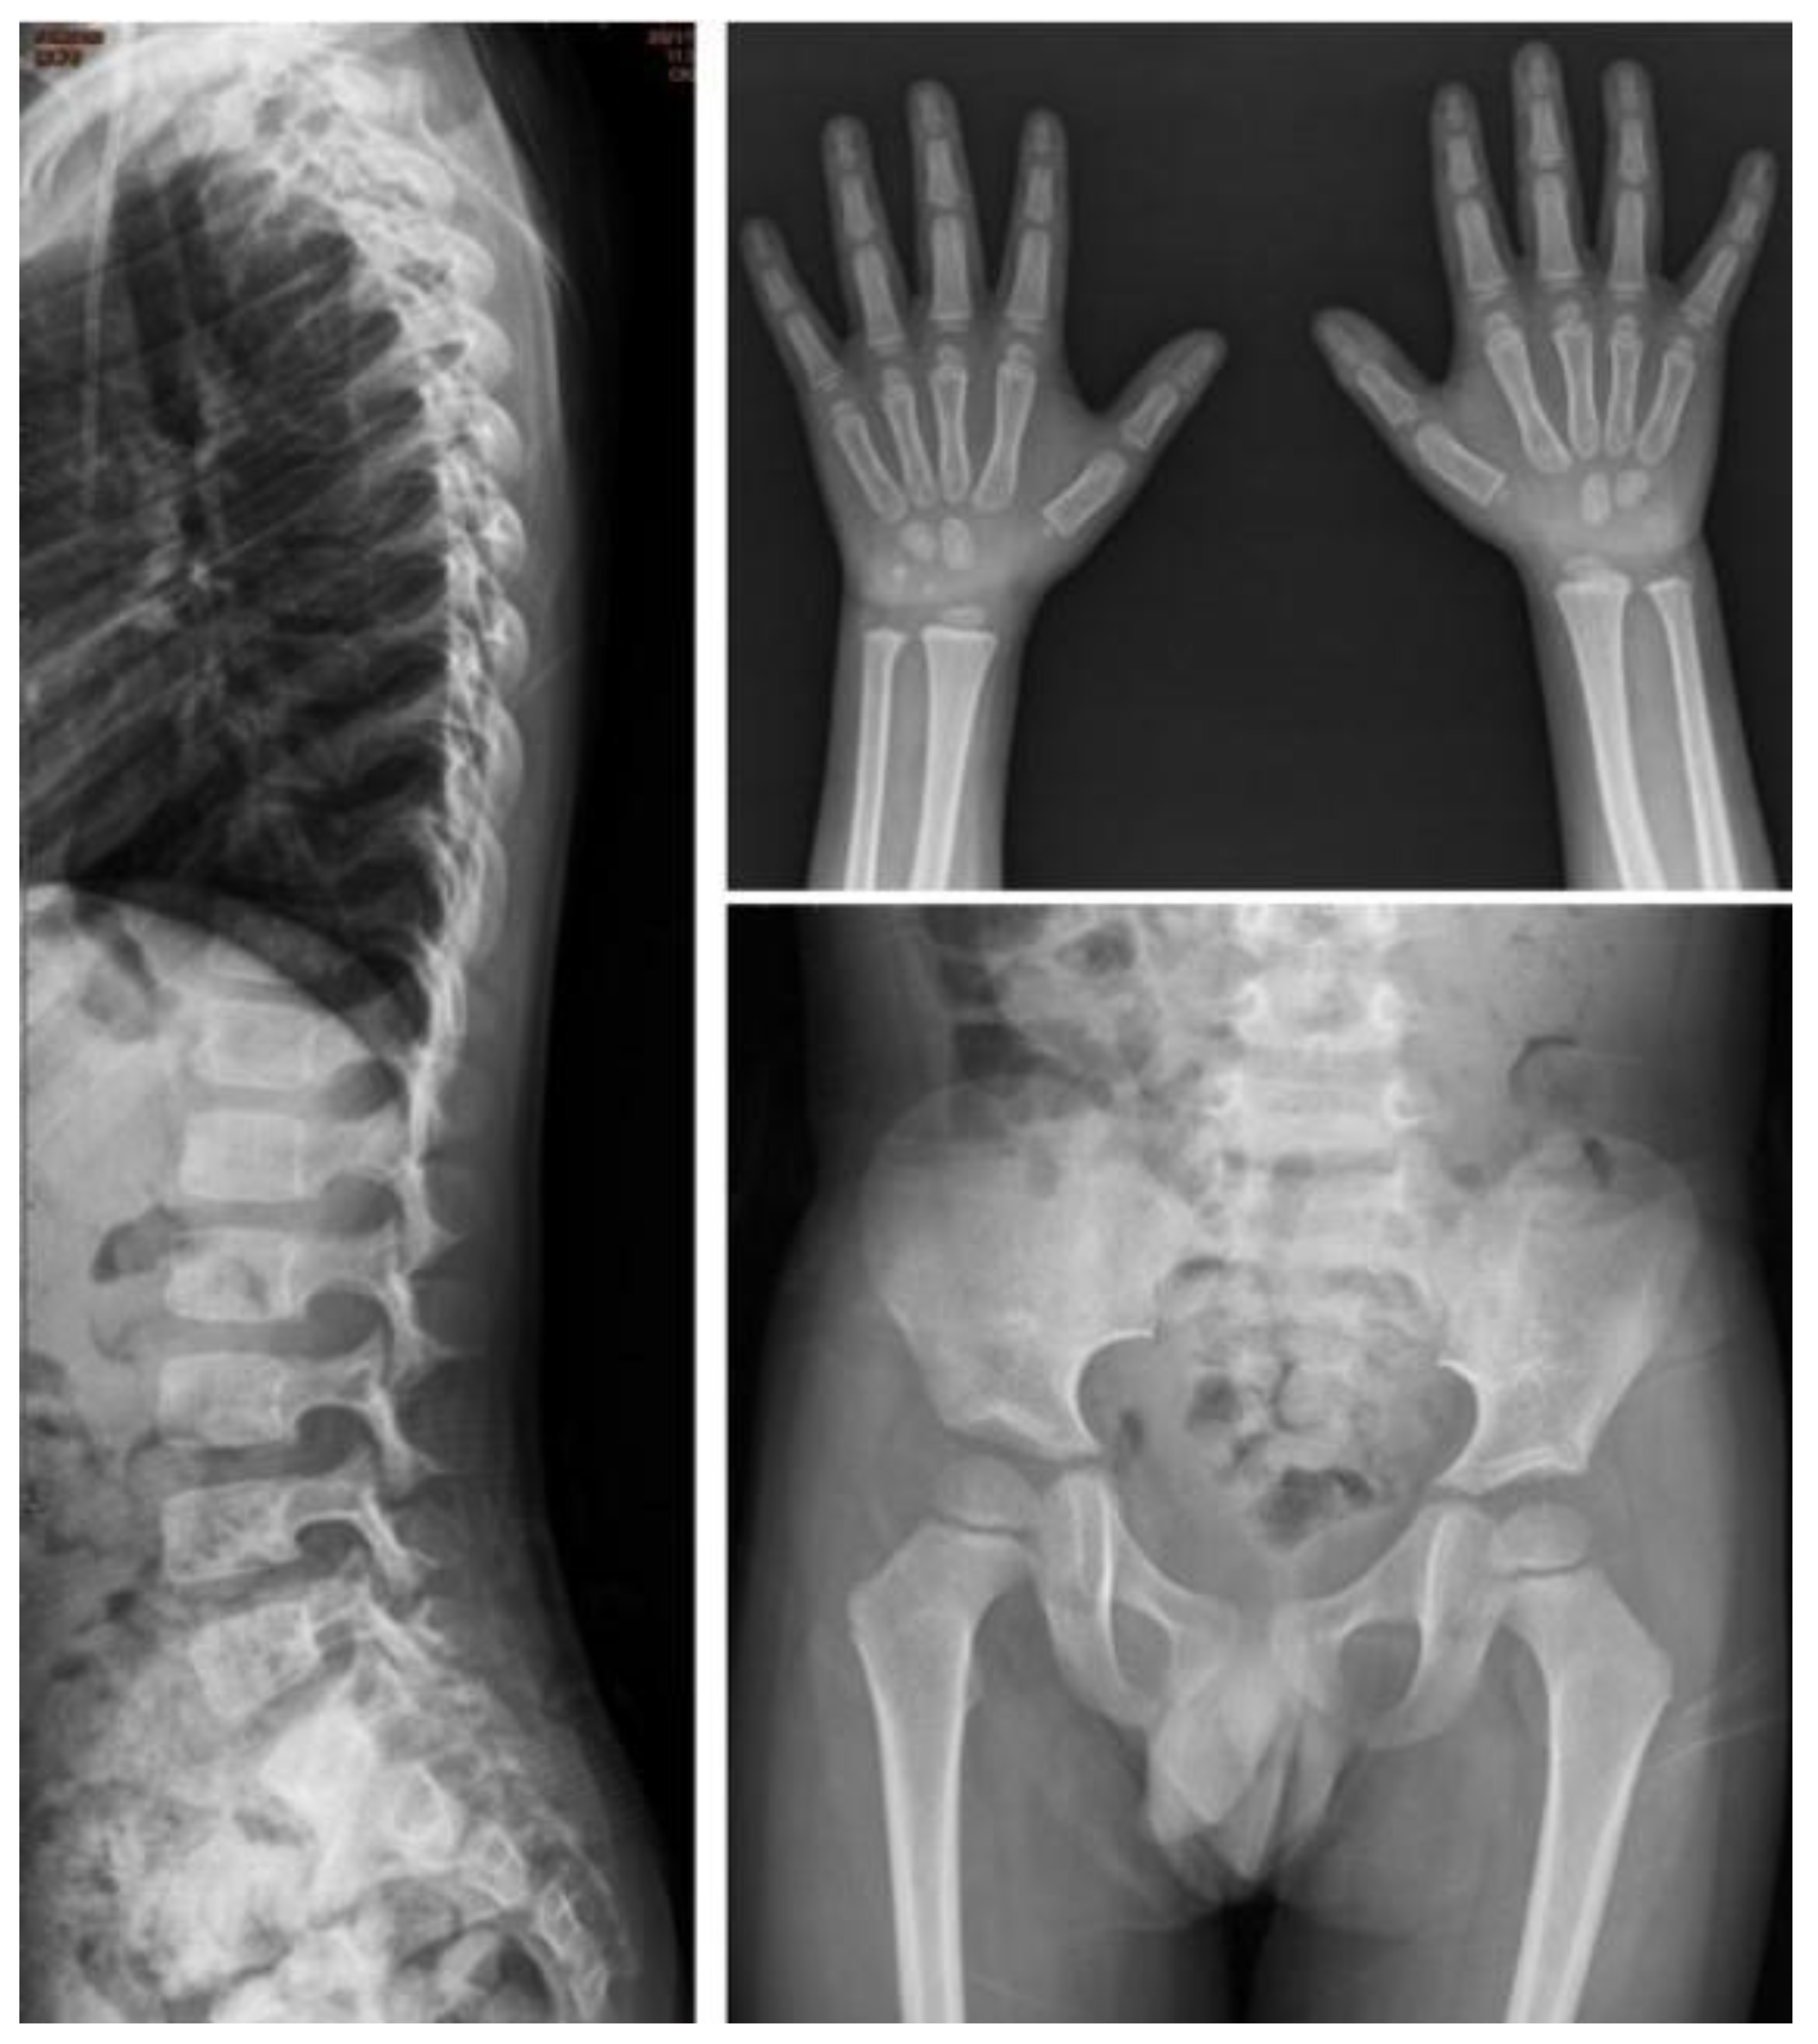

| I-5 | M | c.1400C > T, p.P467L | — | 0.5 | Baseline | 0.2 | 0.27 | 153.16 | 21.4 | 30.01 | 0.11 | Proximal tapering of metacarpal bone with bullet-shaped phalanges. | Normal | Normal | Normal | Normal |

| Follow-up | 3.5 | 7.51 | 18.01 | 0.42 | 3.28 | 2.39 | Suspicious of mild proximal tapering of metacarpal bone with bullet-shaped phalanges. | Multiplex dysostosis of the spine. L-spine vertebral bodies are round. The anterior beaking more at several vertebral bodies of L-spine. | Round iliac wings, inferior tapering of the ilea with not-well developed acetabulum. | Normal | Normal | |||||